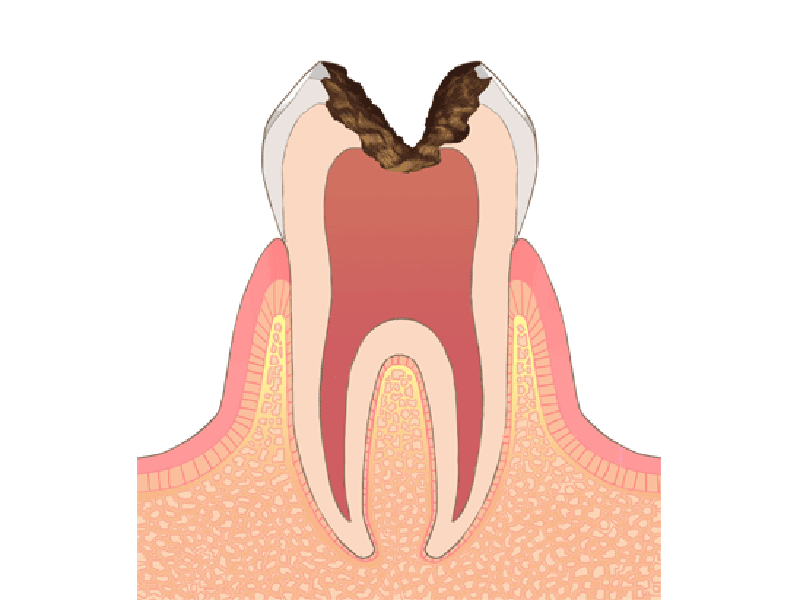

むし歯の進行度別治療方法

神経の近くまでむし歯が進行した場合

この様な場合は、むし歯が中期まで進行している可能性があります。

神経までむし歯が達した場合